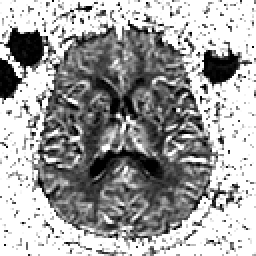

Alzheimer's Disease: SPECT/fMRI overlay -- Slice #5

[Home][Help][Clinical] Slice 5